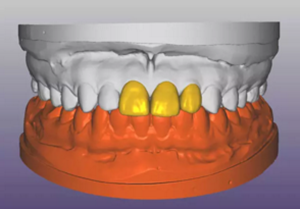

(1)術(shù)前準(zhǔn)備。拍攝臨床照片、拍攝輕開口位CBCT(NewTom)、取聚醚印模灌制超硬石膏模型。 構(gòu)建數(shù)字化模型并設(shè)計修復(fù)體:將超硬石膏模型在口外掃描(Identica? Hybrid),獲取軟硬組織表面形態(tài),構(gòu)建數(shù)字化模型,確認(rèn)咬合情況。根據(jù) 天然牙殘根頸部形態(tài)設(shè)計修復(fù)體頸部形態(tài),使修復(fù)體頸緣輪廓與原有天然牙 一致;按正常牙弓弧度與覆 、覆蓋關(guān)系,結(jié)合紅白美學(xué)等原則確定修復(fù)體 的三維形態(tài)。最后,導(dǎo)入患者面部照片,確認(rèn)模擬修復(fù)效果。 設(shè)計種植體位置并制作多級導(dǎo)板:利用Segma設(shè)計軟件,將CBCT數(shù)據(jù) 和模型掃描數(shù)據(jù)進(jìn)行配準(zhǔn),調(diào)入模擬修復(fù)效果數(shù)據(jù),以修復(fù)為導(dǎo)向設(shè)計種植 方案,設(shè)計種植體螺絲孔開口從修復(fù)體舌窩處穿出,最終實現(xiàn)螺絲固位的一 體化基臺冠修復(fù)。根據(jù)種植體信息設(shè)計多級導(dǎo)板,參考修復(fù)體形態(tài)設(shè)計導(dǎo)板 植入?yún)^(qū)頸緣外形,打印生成種植導(dǎo)板(Segma),并安裝金屬引導(dǎo)環(huán)。 設(shè)計并制作臨時修復(fù)體:如前所述,按照美學(xué)效果和咬合關(guān)系設(shè)計臨 時冠外形,頸部形態(tài)與模型齦緣輪廓一致,保證臨時修復(fù)體在術(shù)后可以封閉 拔牙窩。3顆臨時冠為連冠,齦外展隙適當(dāng)加大,為術(shù)后軟組織生長提供一 定的空間。在臨時冠近兩側(cè)鄰牙的切角處預(yù)留翼板,保證臨時冠戴入時可以 找到準(zhǔn)確的位置。以銑削的方式加工臨時冠(Segma),待種植體植入后 將其在口內(nèi)粘接于臨時基臺上。

圖4 構(gòu)建數(shù)字化模型并設(shè)計修復(fù)體